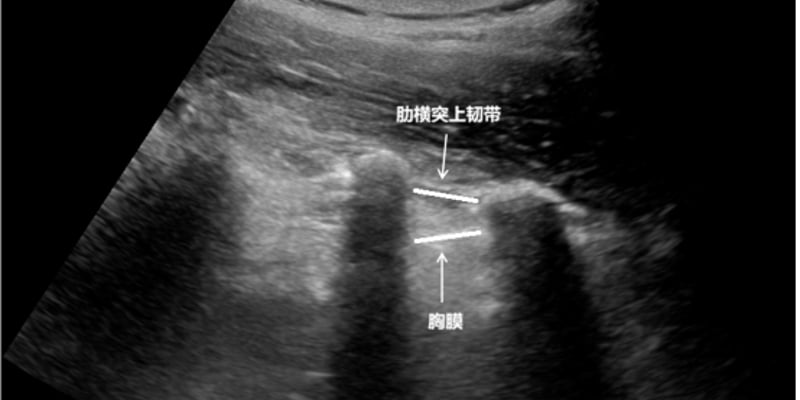

一名27岁女性患者因长期性交后阴道出血及近期间歇性出血就诊。妇科检查和超声影像显示宫颈后唇存在异常回声和丰富的血流信号,提示高度血管化病变。盆腔MRI进一步揭示了宫颈病变。患者随后接受了宫颈环形电切术(LEEP),初步病理诊断为伴有TFE3基因重排的血管周上皮样细胞肿瘤(PEComa)。鉴于病理表现的罕见性,患者寻求了外部专家会诊。经过免疫组化和分子分析的综合评估,最终确诊为腺泡状软组织肉瘤(ASPS)。确诊后,患者接受了腹腔镜全子宫切除术联合双侧输卵管卵巢切除术。术后病理证实残余肿瘤局限于宫颈,无淋巴血管或神经周围侵犯。患者术后未接受辅助治疗,并在三个月的随访期内未观察到肿瘤复发或转移。此病例强调了在罕见肿瘤诊断中,多学科会诊和分子检测的重要性。